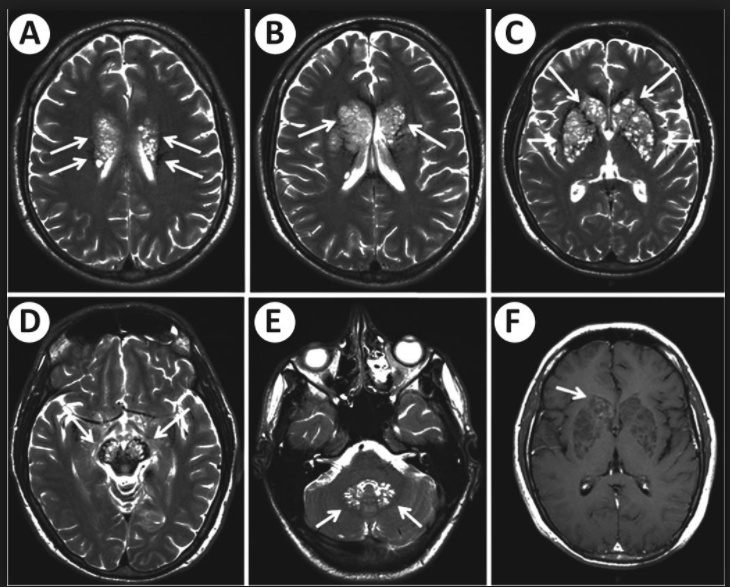

soap bubbles on head: Causes "soap bubble" lesions in gray matter